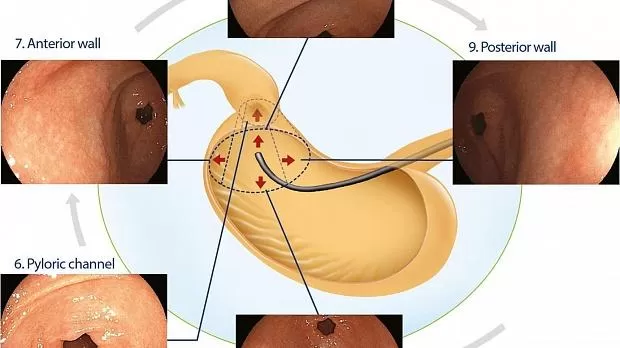

Пилорический канал и антральный отдел желудка

Внутри просвета прицел перемещается к антральному отделу. При адекватном изображении пилорического канала привратник располагается в центре эндоскопического поля с максимумом 2 см окружающей слизистой оболочки, область 6. Затем телескоп осторожно отводят назад, и путем вращения по часовой стрелке достигается крупное документирование антрального отдела желудка: передняя стенка с привратником в районе 3 часов, зона 7; меньшая кривизна с привратником у 6 часов, зона 8; задняя стенка с привратником у 9 часов, зона 9; и большая кривизна с привратником в районе 12 часов, область 10 (рис. 4 ).